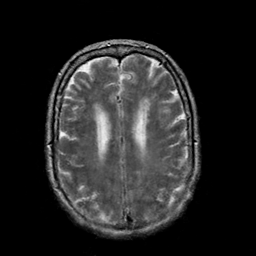

In this paper, we propose a bidirectional learning model, known as dual contrast cycleGAN (DC-cycleGAN), for medical image synthesis from unpaired data. Specifically, a dual contrast (DC) loss is formulated that leverages the advantage of samples from the source domain as negative samples to indirectly build constraints between real source and synthetic images via discriminators, and synthesize images more related to the target domain by enforcing the synthetic images to fall far away from the source domain. In addition, structural similarity index (SSIM) [35] and cross-entropy (CE) [48] are integrated into the DC-cycleGAN structure to avoid disappearing gradient information that is caused by a mean absolute error (MAE) and synthesizing irrelevant images. SSIM considers luminance [35] and CE converges fast as its back-propagation error is less than MSE [28]. As can be seen in Figs. 1 and 2, using SSIM and CE with dual contrast can generate more clear and accurate MR images as compared with that of MAE and MSE, and SSIM and CE without dual contrast loss. Although both SSIM and CE with dual contrast and without dual contrast generate similar CT images, SSIM and CE with dual contrast quantitatively generate better images as shown in Table 4. The experimental results indicate that DC-cycleGAN is able to consider more complex features such as structure in synthesizing images and produce remarkable results as compared with other state-of-the-art methods reported in the literature.

Tables 3 and 4 show the results of MR and CT synthesis, respectively. As can be seen, all components play vital role in both tables. SSIM & CE (w) performs significantly better than other losses in synthesizing MR images. This also can be seen visually in Fig. 1. In contrast, SSIM&CE (w) performs slightly better than SSIM&CE (wo) in synthesizing CT images, both generate more or less similar CT images (see Table 4).